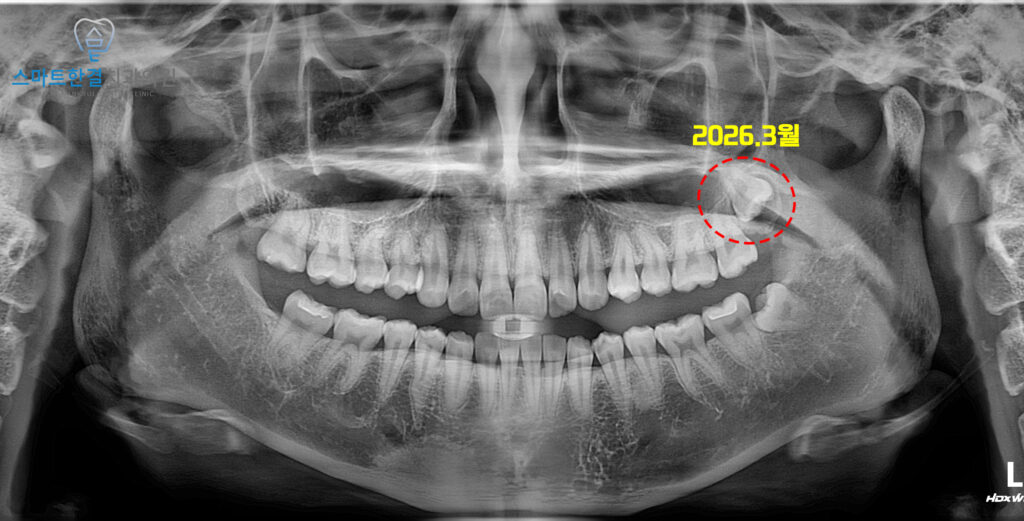

2026.3월

<위쪽 사랑니 낭종 크기 커진 양상>

이후 일 년 뒤 정기검진 위해 재내원하셨는데요.

파노라마를 촬영하여 확인해 보니,

왼쪽 위 사랑니 주변의 낭종이

일 년 전 보다 더 커진 것을 확인할 수 있었어요.

정밀한 확인을 위해 CT도 촬영하여

비교해 보기로 했어요.